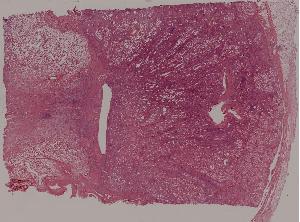

77.慢性肾盂肾炎

低倍视野